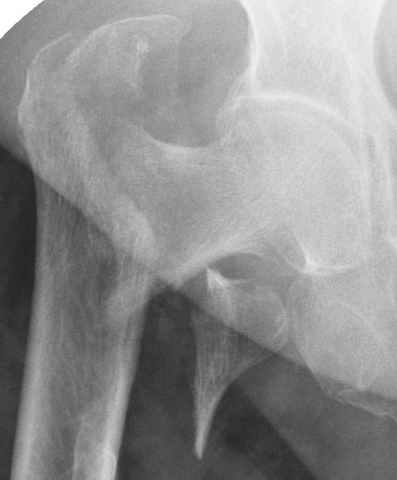

Для молодых больных выбрал бы тактику fixed angled device 95 degree Blade Plate, техника непрямого метода репозиции, который описал в своей книге Jeff Mast, Planning and Reduction Technique in Fracture Surgery ( method of Inderect Reduction), репозиция и фиксация происходит за счет фиксации головки бедра к femoral shaft с помощью пластины, а что в середине должны репонироваться без больших усилии и без разрушения мягкотканого соединения c медиальной стороны.

Пластина дает свободу:

Valgus-varus; extention- flexion, зависит только от образования канала для blade на головке.

Ap pelvis Rt sub-intra trochanteric Fracture, AP Rt hip, Postop Blade Fixation